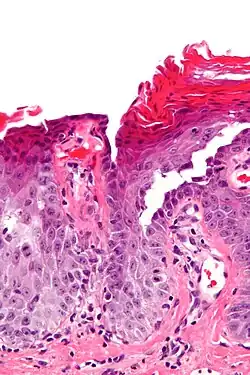

| Micrograph of transient acantholytic dermatosis, showing subcorneal separation and acantholysis. H&E stain. | |

Grover's disease (GD) is a polymorphic, pruritic, papulovesicular dermatosis characterized histologically by acantholysis[2]: 529 with or without dyskeratosis.[3] Once confirmed, most cases of Grover's disease last six to twelve months, which is why it was originally called "transient". However it may last much longer. Nevertheless, it is not to be confused with relapsing linear acantholytic dermatosis.

Grover's may be suspected by its appearance, but since it has such a characteristic appearance under the microscope a shave skin or punch biopsy is often performed.